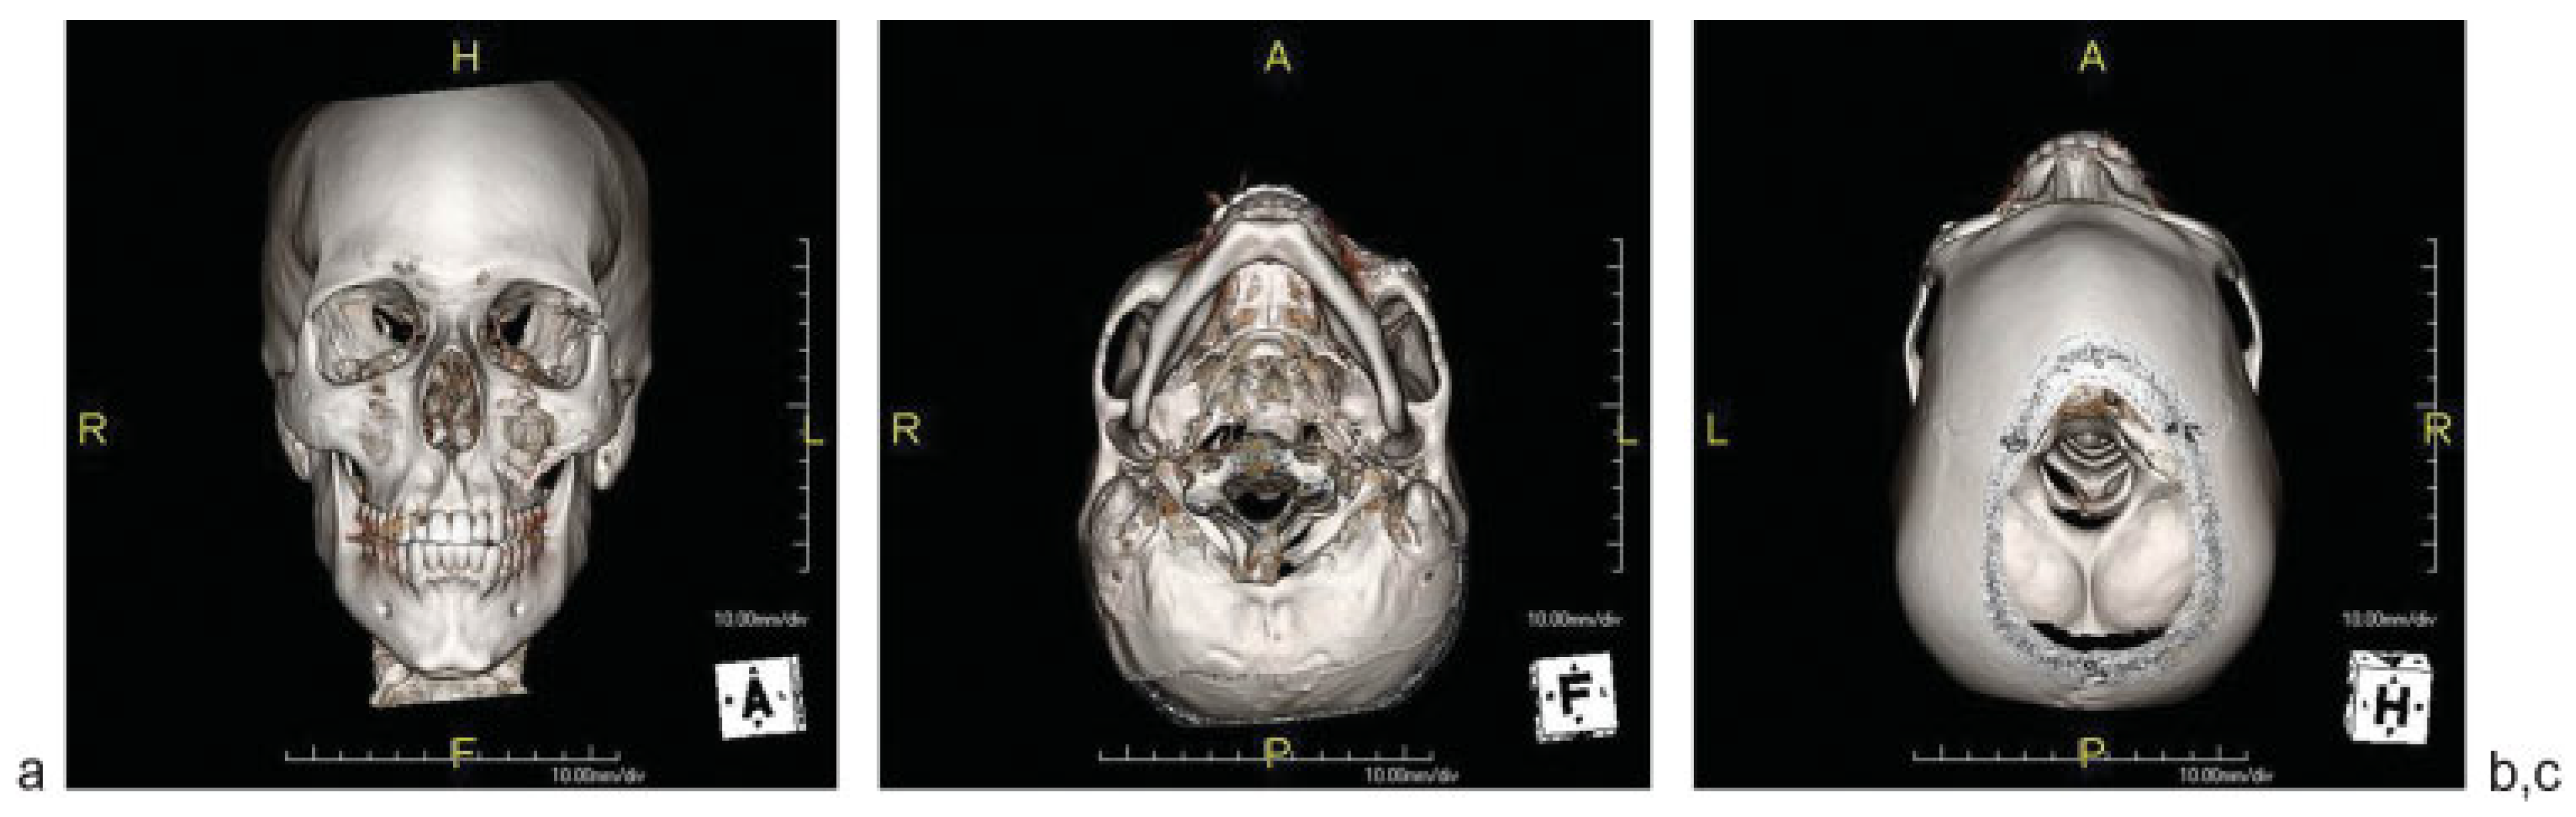

Postoperative imaging demonstrated anatomic reduction of the OZMC at all articulations (Figure 7 and Figure 8).

Figure 8. Three-dimensional reformations, demonstrating restoration of zygomatic projection and symmetry in (a) frontal, (b) submentovertex, and (c) bird’s eye views.